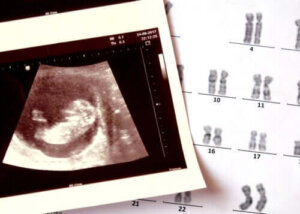

Bezmózgowie to choroba wrodzona polegająca na braku rozwoju niektórych części układu nerwowego i czaszki dziecka.

Ten stan zaliczany jest do wad cewy nerwowej, grupy wrodzonych patologii, która obejmuje również rozszczep kręgosłupa.

Zmiany w chromosomach (strukturach, w których znajdują się wszystkie geny komórek) i niektóre specyficzne mutacje mogą przyczynić się do jego wystąpienia. Jako możliwy wyznacznik zbadano również narażenie na niektóre toksyny środowiskowe. Jednak wyniki badań nie są w tej chwili rozstrzygające.